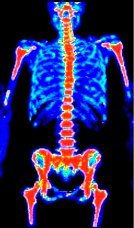

Pour simplifier, cet examen consiste à injecter du sucre radioactif (généralement du 18 Fluoro Desoxy Glucose ou 18 FDG) dans le sang et à le détecter grâce à une caméra spéciale (TEP : tomographie par émission de positon). Les cellules cancéreuses qui se nourrissent de beaucoup plus de sucre que les cellules normales apparaissent alors en couleurs sur les images.